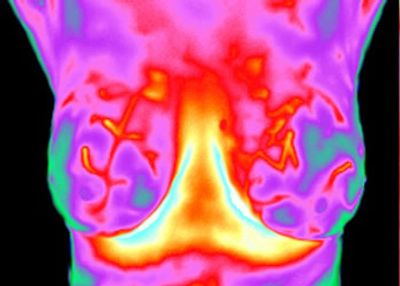

The second classification in the Marseille system defines a thermal profile of the breasts that features symmetrical, non-complex and moderately hyperthermic vascular patterns. All thermal features demonstrate normal and adaptive response to the autonomic challenge. The TH-2 classification indicates no thermology signs or criteria associated with breast cancer. However, while very unlikely, it is possible that some small cancerous tumors may be in a quiescent state and their vascular development could be minimal. In this event, the very minor thermal characteristics may evade discernment, especially in an initial study. The high-energy vascular patterns of the TH-2 classification are associated with benign glandular hypertrophy as may be caused by elevated blood levels of estrogens or disproportionate blood levels of estrogens to progesterones. The TH-2 classification is common during pregnancy and lactation. This thermology category is also associated with the development of cysts and fibro-adenomas. This will modify the classification as TH-2F. Annual comparative thermology restudy is recommended and more frequent restudies may be clinically indicated.